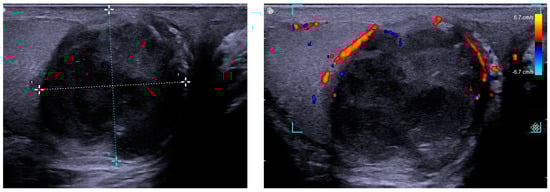

2. Case Presentation